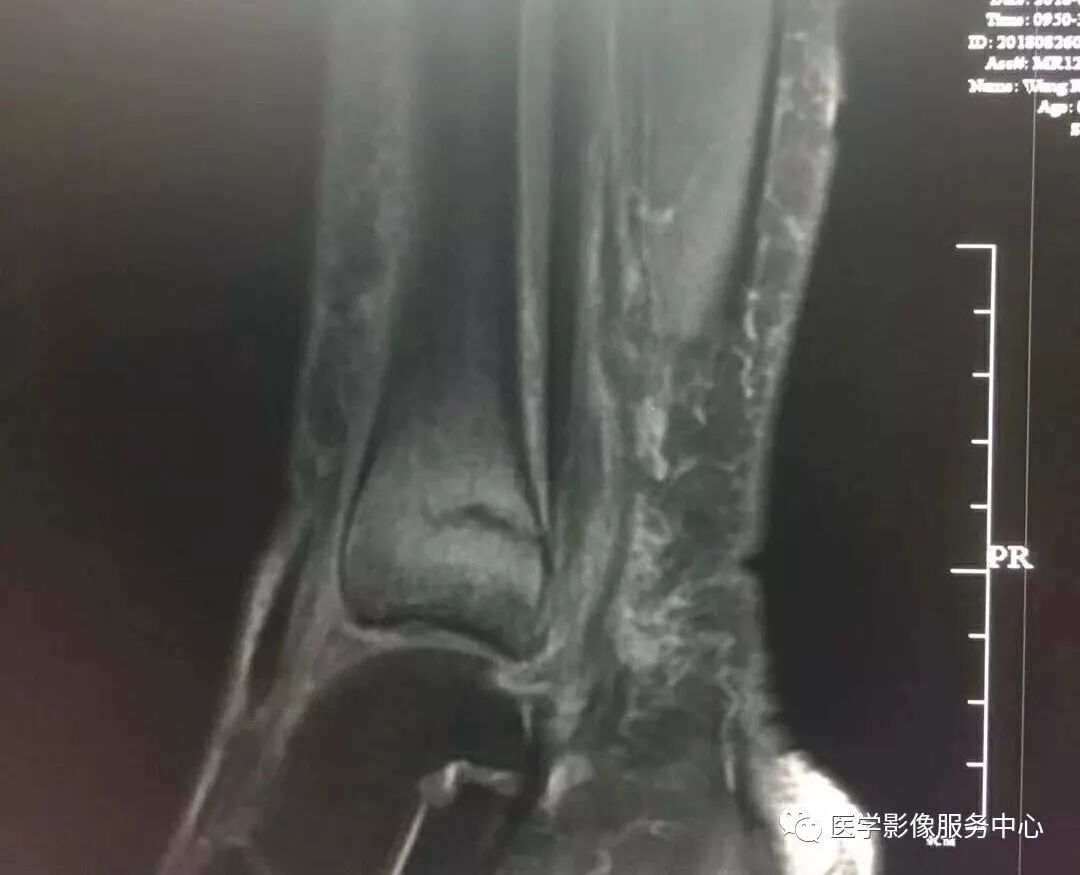

Pilon骨折常常伴随极度粉碎的骨折和严重的软组织损伤,选择合适的手术入路就成了手术的关键。